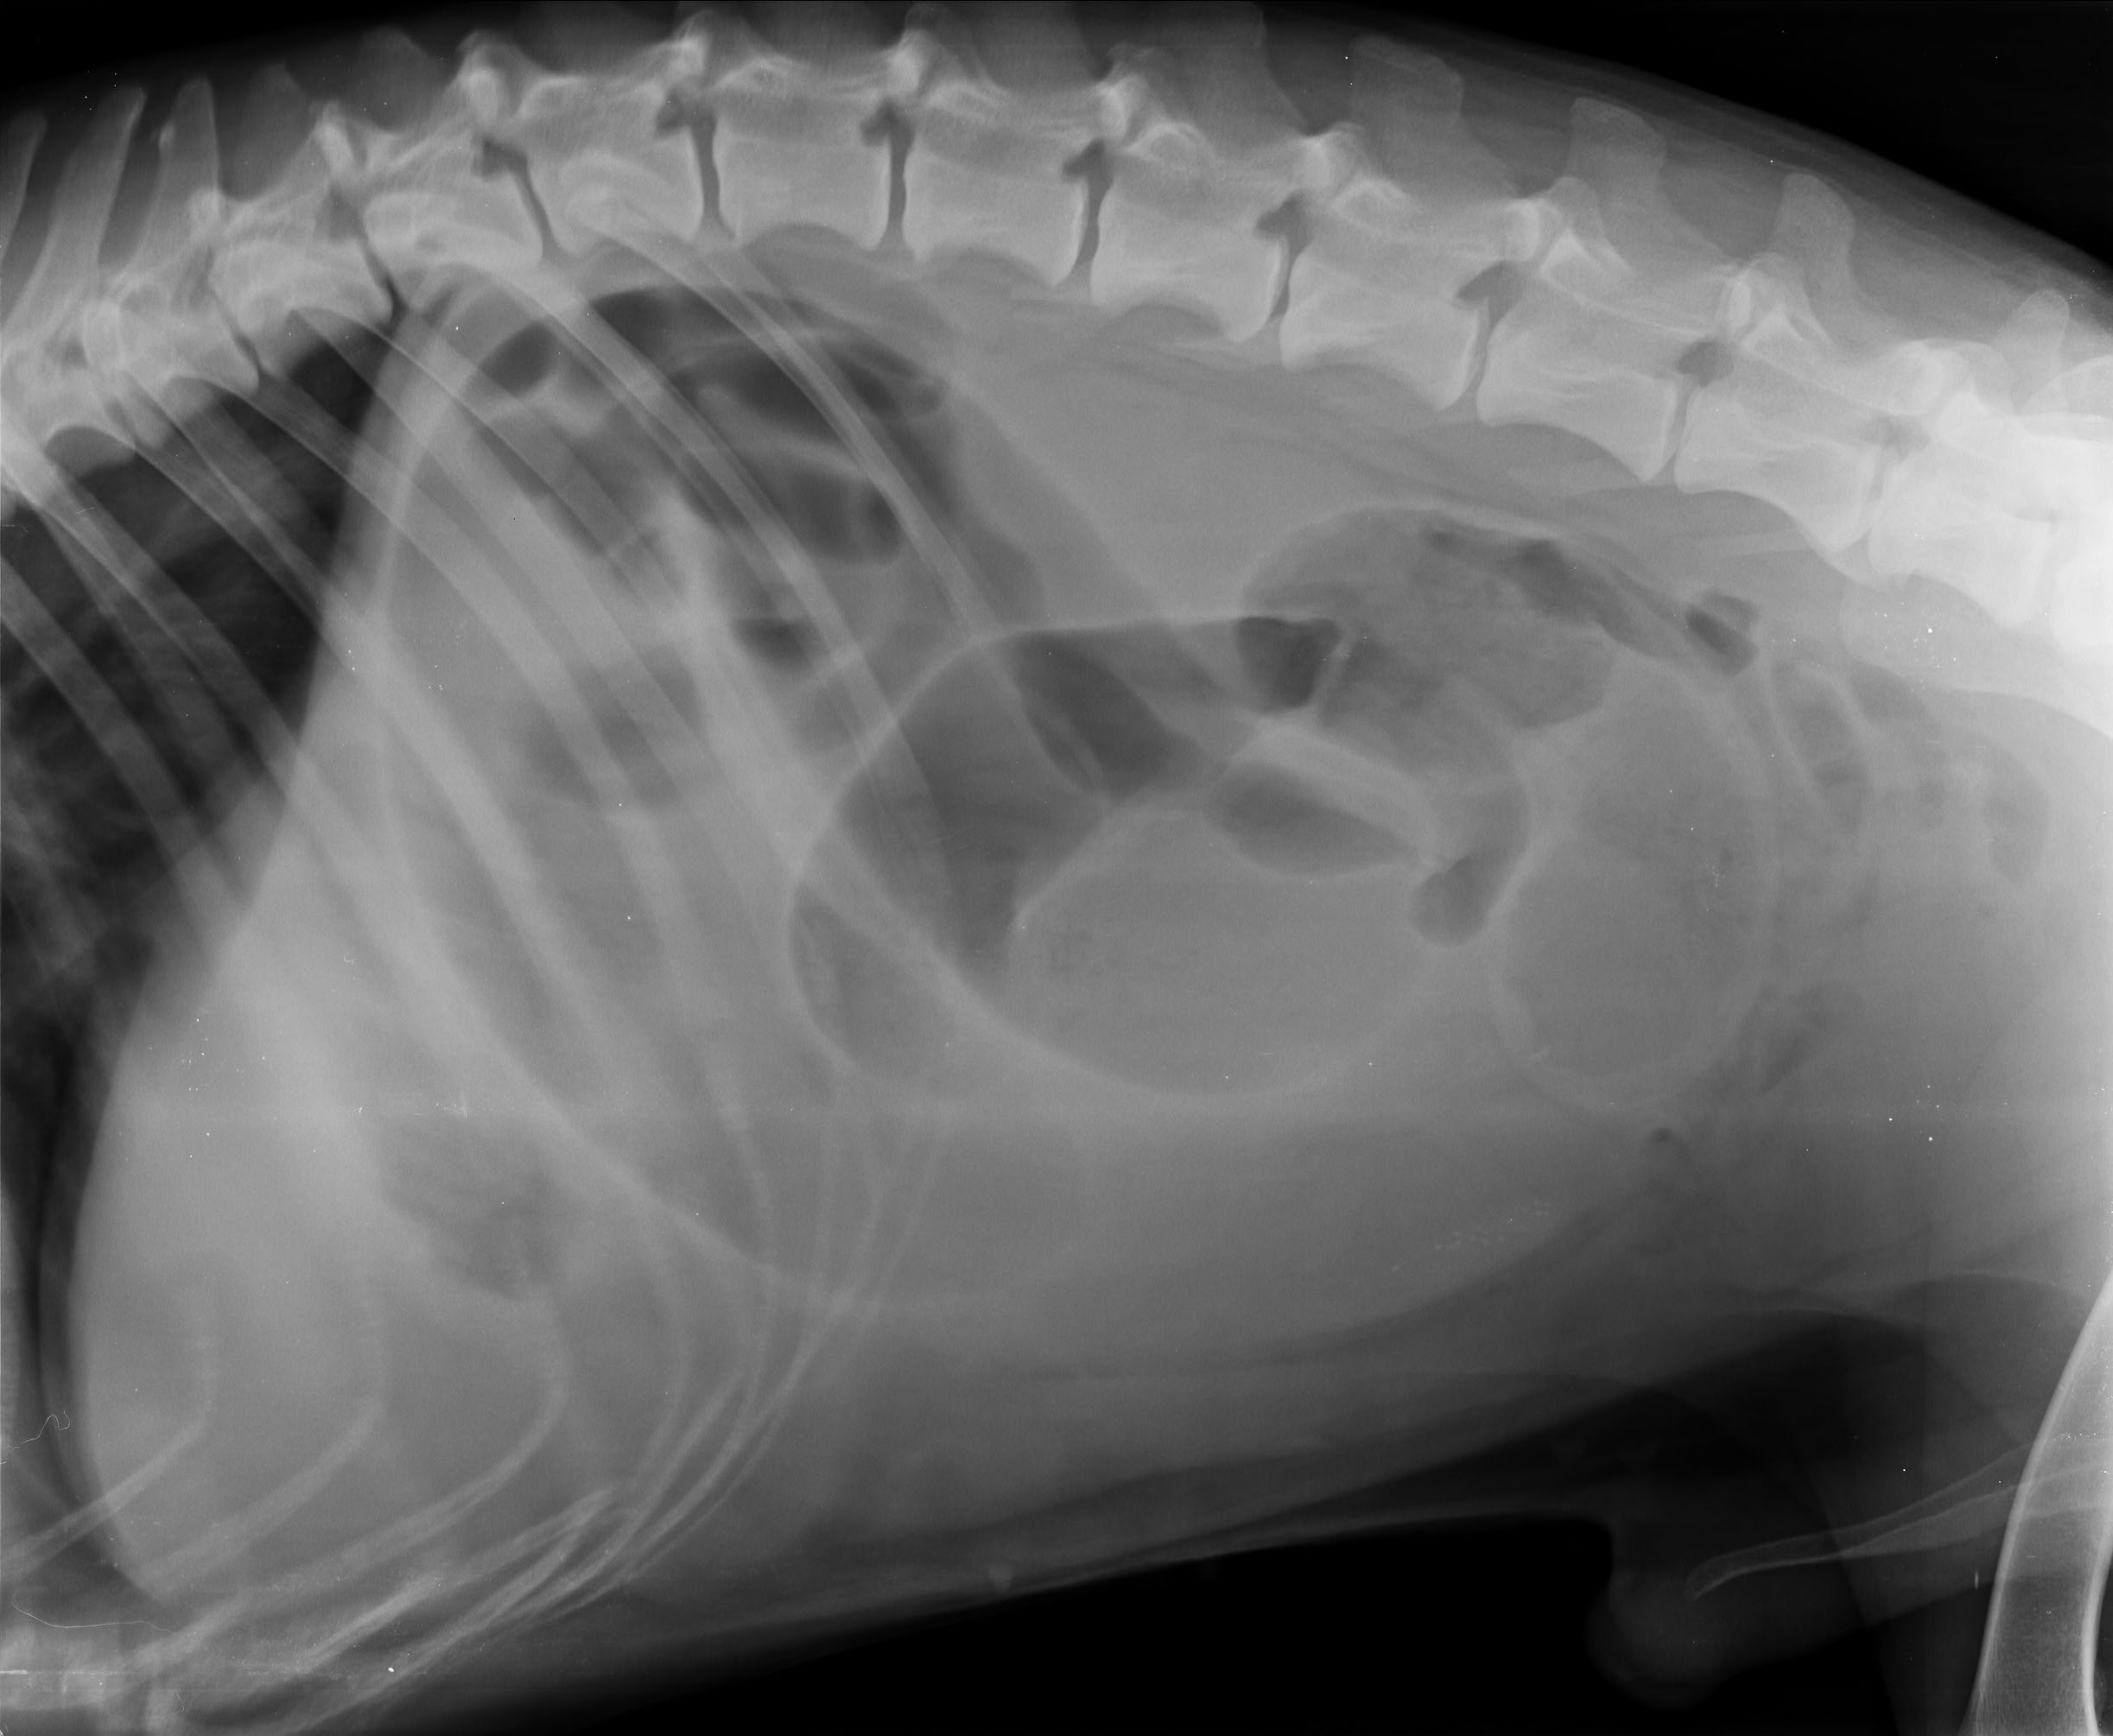

nisam siguran da sam takvu sliku rendgena gledao na monitoru u ambulanti Lonjica, ali nigdje nema moga imena ili imena moga psa

drugi rtg

Goran u tijeku razgovora indirektno potvrđuje da ultrazvuk koji se navodi u nalazu nije rađen 13.4.2021., već kao kad je pas bio pod anestezijom ili eutaniziran jer spominje da su radili Zrinka i on. To je dokaz lažiranog nalaza i da je pas podvrgnut operaciji na osnovu rendgena, a ne ultrazvuka ili laparoskopije. U dijelu gdje Goran kaže da nemaju nalaz ultrazvuka jer se gleda na monitoru, ali da se na rendgenu bolje vidi, a Zrinka to prije operacije nije vidjela, znači samo jedno, da svatko vidi drugačije ili da to nisu rendgenske snimke moga psa, da su mi i to podvalili.

Na rendgen snimkama nema moga imenam prezimena ili imena moga psa.